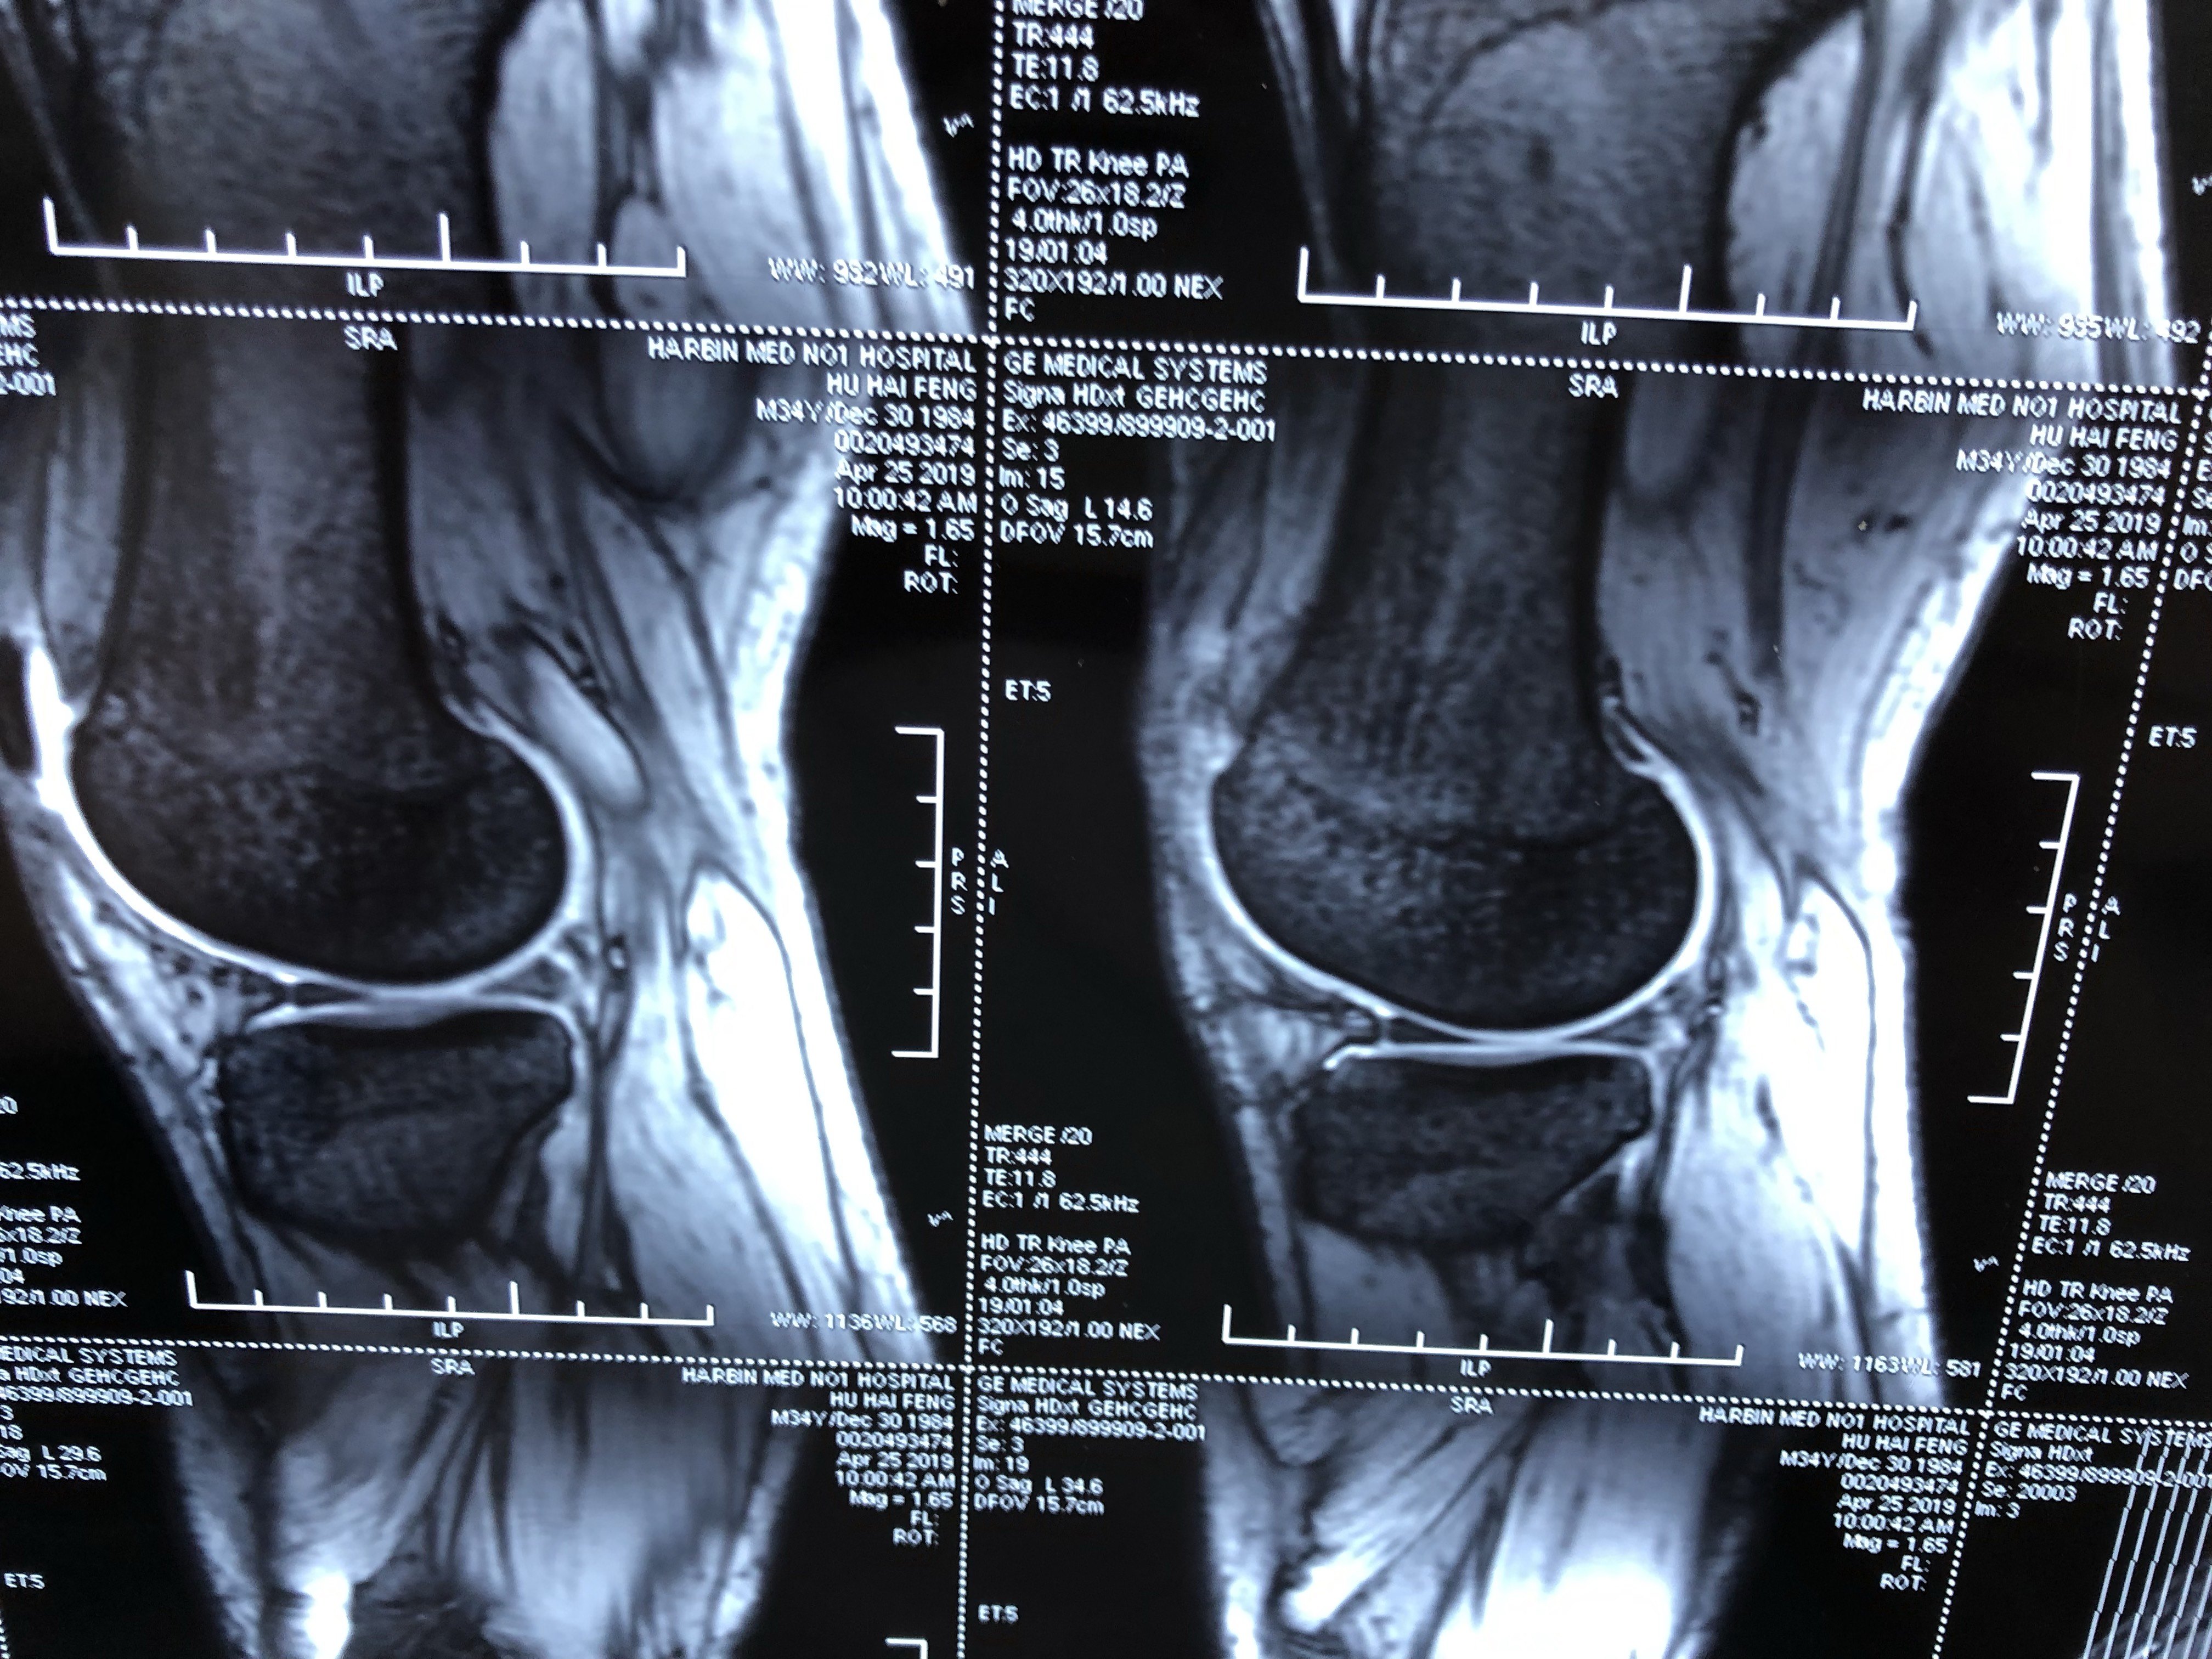

Mriでは前十字靭帯の損傷を高い精度で確認できると同時に、診察では見つけにくい半月板損傷や軟骨損傷を調べることができます(図1)。 図11)mri:膝前十字靭帯損傷 図12)mri:半月板損傷 診察肩関節mriの正常解剖(斜冠状断像) 肩関節mriの正常解剖(矢状断像) 胸部ct(肺野条件) 胸部ct(縦隔条件O脚傾向の人が多いので膝の内側の軟骨がすり減る場合が多いとされています。欧米人では外側型もあり、お皿の骨(膝蓋骨)の軟骨が摩耗する型もあり、各型混在しています。 発生要因 日々の関節の摩耗による場合と、半月板や靭帯損傷後に関節変化が出る場合があります。 肥満者のほうが